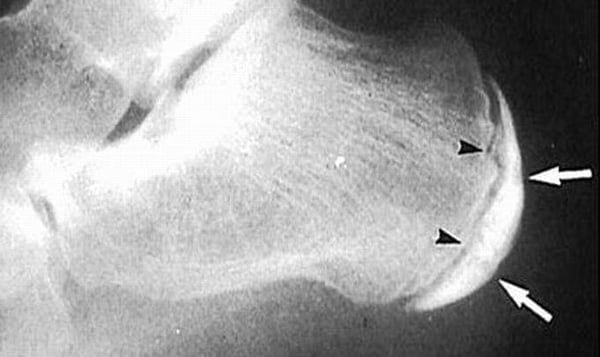

Он диагностируется при обострениях артрита, подагры, остеоартроза. Для выявления патологии проводится ряд инструментальных и лабораторных исследований: рентгенография, МРТ, КТ, артроскопия. Лечение бурсита пятки — обычно консервативное, с использованием глюкокортикостероидов, антибиотиков, НПВП, физиопроцедур. При неэффективности такой терапии больному показано проведение хирургической операции.

Перед началом лечения бурсита пятки проводятся диагностические мероприятия. Заподозрить патологию ортопед может на основании жалоб пациента и осмотра стопы. Отек, боль и покраснение кожи указывает на протекающий в ноге воспалительный процесс. Но такие внешние признаки характерны для многих суставных патологий, поэтому проводится дифференциальная диагностика:

- рентгенография;